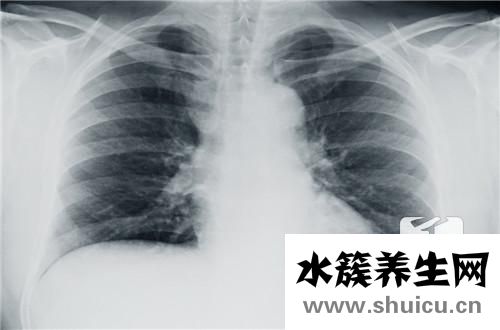

胸部是人體自然比照優(yōu)良的位置。運用X線對心臟及肺的透過工作能力不一樣,在X線片或顯示屏上導致相對密度不一樣的影象,不需造影檢查就可以把肺內變病和心臟輪廊清晰地顯示信息出去。因此,胸部的X線檢查已變成運用最普遍的確診方式之一。

常見的胸部X線檢查方式有透視和拍片子二種。若有模糊不清原因的發(fā)熱、長期咳嗽、氣短、喘鳴、咯血、烏青、心悸及膈肌脊柱有畸型時,經(jīng)醫(yī)生檢查覺得有必要,都能夠作胸部X線檢查。

胸部X線檢查針對小孩支氣管異物的確診有較高的精確性。針對肺部炎癥、肺不張、肺氣腫、氣胸、胸腔積液等也都能顯示信息,并掌握變病范疇和水平。一樣能顯示信息心臟和大血管的尺寸和形狀,橫膈變病如膈膨升、橫膈疝等。除此之外,胸部線片還可觀查到胸部骨骼的改變。但胸部x光片查驗有一定的局限,縱膈黑影內的人體器官和組織,如心臟、主動脈、靜脈、淋巴結、神經(jīng)、食道、支氣管等,除開支氣管外其他均不可以辨別。